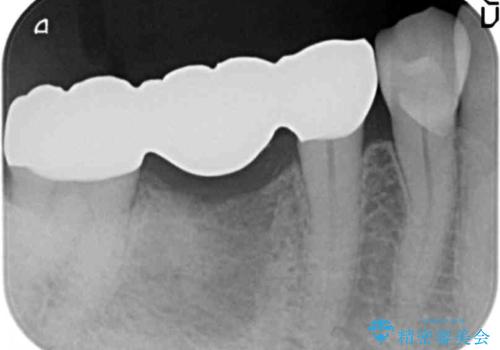

かみ合わせが強いのでフルジルコニアクラウンベレッツァを用いたブリッジを製作。

ブリッジは抜歯した当日に仮歯を装着できるのでインプラントや義歯と比べ早期に咬合機能が回復可能です。